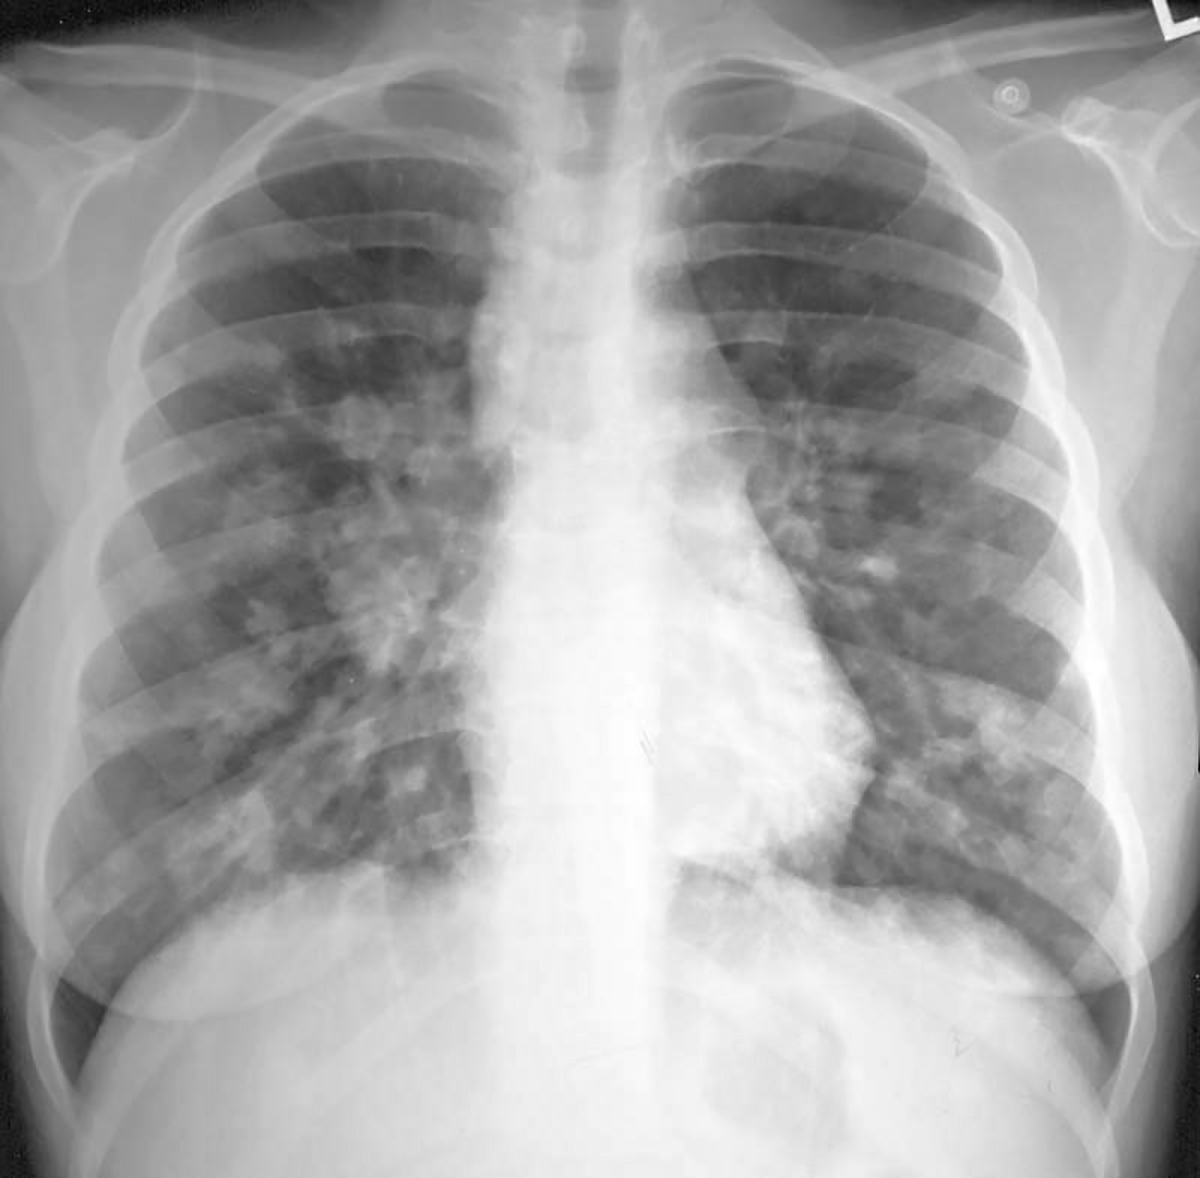

Topic 7

advanced case for mediastinal widening

Further Explanation:

alternative diagnosis for mediastinal widening